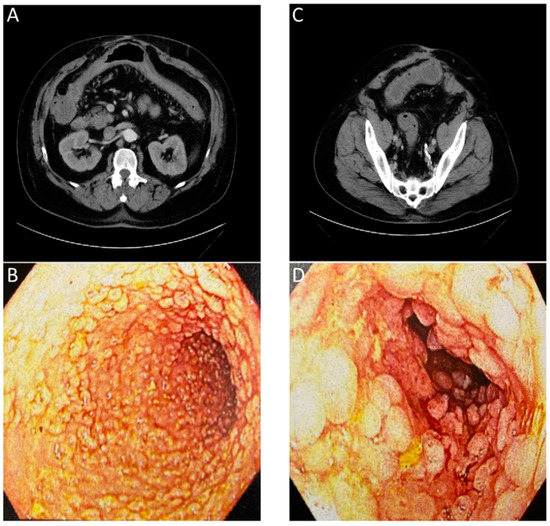

Historically, tests using blood, stool, or biopsied tissue samples have been paired with invasive imaging techniques, such as endoscopy, to diagnose and assess patient GI disease [124]. Currently available invasive and non-invasive imaging techniques such as endoscopy, CT, MRI, and US, can show the macroscopic structural abnormalities associated with inflammatory bowel disease such as bowel wall thickening, abscesses, or fistulas to identify the scope of disease [125]. When combining multiple standard imaging modalities, the presence of inter-clinician reader variability and the lack of molecular information contained in the images (Figure 4) often requires a biopsy for an accurate diagnosis. In the context of Figure 4, the numerous lesions within the colon result in a higher potential of a biopsy sampling error and the possibility to miss areas of early-stage colon cancer.

Figure 4. Images of a patient with history of chronic diarrhea that is occasionally bloody. CT ordered for unrelated reasons incidentally showed non-specific inflammation. Correlation with endoscopy showed substantial chronic inflammation. (A) CT with arrows showing inflammation of transverse colon. (B) Endoscopic images of transverse colon with diffuse pseudopolyps. (C) CT with arrows showing inflammation of sigmoid colon. (D) Endoscopic images of sigmoid colon with diffuse pseudopolyps. The lack of an inflammation or cancer specific contrast agent for the CT or endoscopic evaluation required a biopsy to confirm a lack of neoplasia.